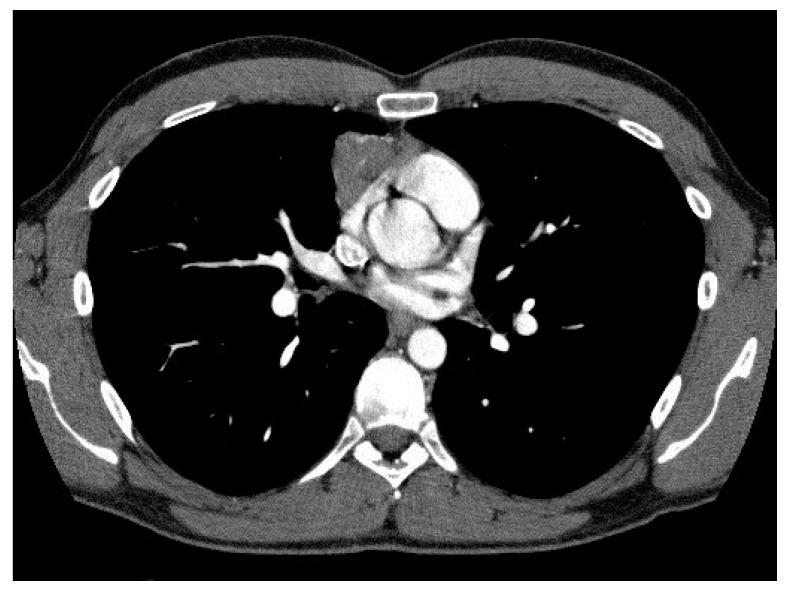

计算机断层扫描参数与外科治疗胸腺瘤的组织学、分期和预后的相关性。

Correlation of Computed Tomography Parameters with Histology, Stage and Prognosis in Surgically Treated Thymomas.

: The histological classification and staging of thymic tumors remains a matter of debate. The correlation of computed tomography (CT) parameters with tumor histology and stage also still has to be completely assessed. The aim of this study was therefore to analyze the correlation of radiological parameters with histological and staging classifications of thymomas evaluating their prognostic role. : Data of 50 patients with thymoma submitted to a complete surgical treatment between 2005 and 2015 were retrospectively analyzed. Tumors were classified according to the WHO and Suster and Moran (S&M) histological classifications and to the Masaoka-Koga and tumor, node and metastases (TNM) staging systems. The correlation of CT features with histology and stage and the prognostic role of histopathological and radiological features were assessed. : Five-year overall (OS) and disease-free survival (DFS) were 90.3% and 81.1%, respectively. A significant correlation of DFS with the Masaoka-Koga ( = 0.001) and TNM staging systems ( = 0.002) and with the S&M ( = 0.02) and WHO histological classifications ( = 0.04) was observed. CT scan features correlated with tumor stage, histology and prognosis. Moderately differentiated tumors (WHO B3) had a significantly higher incidence of irregular shape and contours ( = 0.002 and = 0.001, respectively) and pericardial contact ( = 0.036). A larger tumor volume ( = 0.03) and a greater length of pleural contact ( = 0.04) adversely influenced DFS. The presence of pleural ( < 0.001) or lung invasion ( = 0.02) and of pleural effusion ( = 0.004) was associated with a significantly worse OS. : Pre-operative CT scan parameters correlate with stage and histology, and have a prognostic role in surgically treated thymomas.

摘要

胸腺肿瘤的组织学分类和分期仍然存在争议。计算机断层扫描(CT)参数与肿瘤组织学和分期的相关性也仍有待完全评估。因此,本研究旨在分析影像学参数与胸腺瘤组织学和分期分类的相关性,评估其预后作用。

回顾性分析了 2005 年至 2015 年间接受完全手术治疗的 50 例胸腺瘤患者的数据。肿瘤根据世界卫生组织(WHO)和 Suster and Moran(S&M)组织学分类以及 Masaoka-Koga 和肿瘤、淋巴结和转移(TNM)分期系统进行分类。评估了 CT 特征与组织学和分期的相关性,以及组织病理学和影像学特征的预后作用。

5 年总生存率(OS)和无病生存率(DFS)分别为 90.3%和 81.1%。DFS 与 Masaoka-Koga( = 0.001)和 TNM 分期系统( = 0.002)以及 S&M( = 0.02)和 WHO 组织学分类( = 0.04)显著相关。CT 扫描特征与肿瘤分期、组织学和预后相关。中度分化肿瘤(WHO B3)更常出现不规则形状和轮廓( = 0.002 和 = 0.001)和心包接触( = 0.036)。较大的肿瘤体积( = 0.03)和更大的胸膜接触长度( = 0.04)对 DFS 有不利影响。存在胸膜( < 0.001)或肺侵犯( = 0.02)和胸腔积液( = 0.004)与 OS 显著相关。

术前 CT 扫描参数与分期和组织学相关,对手术治疗的胸腺瘤具有预后作用。